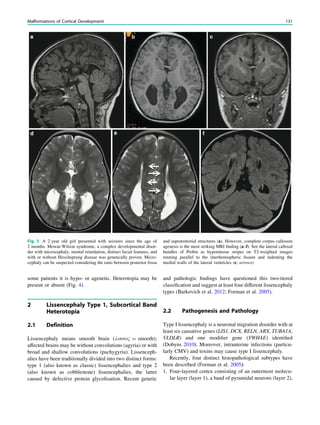

Contents

1 Introduction.......................................................................... 29

2 Theoretical Considerations................................................. 29

3 Clinical Practice................................................................... 30

4 Requirements for MR Quality........................................... 32

4.1 Orientation ............................................................................. 32

4.2 Spatial Resolution.................................................................. 32